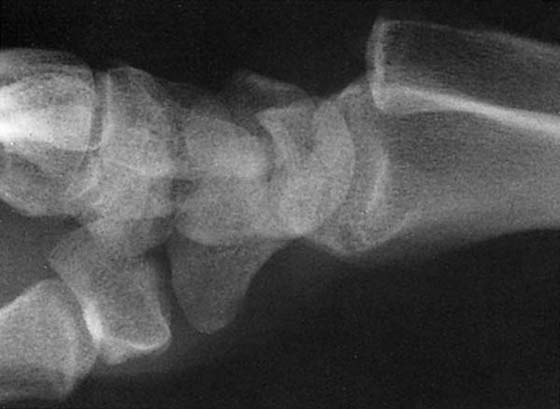

The diagnosis of many patterns of carpal instability can be established by routine radiographic findings. The lateral projection is useful in evaluating both DISI and VISI. In DISI, the lunate is tilted dorsally, with the scaphoid displaced vertically. The angle of intersection between the main longitudinal axis (along the radius, lunate, capitate, and third metacarpal) and the long axis of the scaphoid is greater than 60 degrees where it should normally be 30 to 60 degrees. The radioscapholunate ligament should be evaluated for tears. This injury is typically degenerative in origin and is thought to be the sequela of trauma to the outstretched hand in a young adult. In VISI, the lunate is flexed toward the palm, and the angle between the two longitudinal axes is less than 30 degrees. Note that this finding may be normal if bilateral and in a young female patient. VISI is less common than DISI overall. Most cases are thought to be degenerative in origin, although there is an association with RA. These patterns must also be carefully interpreted on sagittal MRI as the lunate may appear more dorsally tilted, mimicking a DISI pattern in otherwise normal wrists.36

Fracture

Most displaced wrist fractures can be adequately assessed by plain film. Frontal and lateral views are routine projections, with radiographs obtained during radial and ulnar deviation helpful in the evaluation of the carpal bones. In addition to evaluation for carpal fracture, the orientation of the carpal rows and the intercarpal relationships are important in the assessment of carpal instability. Fractures of the scaphoid are most common, with classification and prognosis for healing or complications based on the location of the fracture line and displacement of the fracture. Isolated fractures of the triquetrum (dorsal surface), lunate, and hamate are less common but also are seen.

The most commonly suggested occult fracture of the wrist involves the scaphoid. In the clinical setting, advanced imaging is often required because scaphoid fractures are difficult to visualize on routine radiographs. Proper radiographic evaluation of the scaphoid has been proposed as requiring four views: a PA in ulnar deviation with fist position, a lateral view, and oblique views with 60 degrees of pronation and supination.62 In the past, scintigraphy, routine tomography, and CT had been used to examine occult fractures, but even in cases with negative CT or tomographs, patients often were treated as if a true fracture were present, if the clinical suspicion was high enough. Treatment was withdrawn if follow-up radiographs remained negative.

More recently, MRI has become the test of choice to assess for the presence of a scaphoid fracture, having been found to have sensitivity and specificity of 95% to 100%, with 100% interobserver agreement.63 In patients in whom scaphoid fractures are clinically suggested, MRI can clearly demonstrate the abnormality, which appears as a dark, linear fracture line on T1-weighted images. It also has the advantage of showing other associated occult fractures, usually involving the triquetrum or distal radius. The MRI protocol should include coronal T1 and STIR images. If the STIR images are negative, a fracture can be confidently excluded. Many patients with suggested scaphoid fractures have only soft tissue injuries, including collateral ligament tears, peripheral TFCC tears, radial TFCC avulsions, and SL or LT ligament tears.